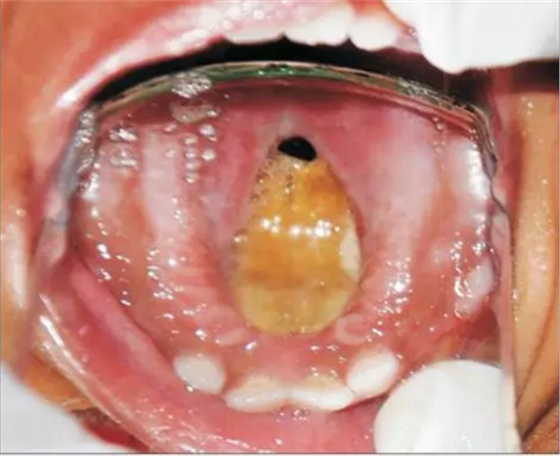

患者為18個(gè)月齡的幼兒,主訴為口腔上腭大面積潰瘍伴鼻腔反流及口腔異味。患兒1個(gè)月前曾在外院治療過肺炎,治療過后一個(gè)月,患兒家長發(fā)現(xiàn)患兒上腭出現(xiàn)一小潰瘍并再一次就診。潰瘍?cè)谌靸?nèi)顯著增大并導(dǎo)致上腭穿孔。患兒出現(xiàn)吞咽困難及鼻腔反流等癥狀。為求治療穿孔及相關(guān)癥狀及預(yù)防吸入性肺炎來我院就診?;純簺]有糖尿病、惡性血液病等病史,也沒有鼻竇炎或流涕等癥狀??趦?nèi)檢查發(fā)現(xiàn)上腭一暴露骨面的巨大潰瘍,范圍從腭中縫至軟腭,局部穿孔?;純嚎诘?、舌、頰粘膜、唇、鼻中隔皆正常,上頜乳切牙、乳側(cè)切牙、左下頜第一乳磨牙已萌出。

口內(nèi)咬合片可見上頜3×4cm大小低密度影,上頜中切牙恒牙胚移位。

初步診斷為口腔毛霉菌病。取部分軟腭組織做病理學(xué)檢查。病理檢查顯示組織中含有大量無包膜的真菌、壞死血管組織,結(jié)果支持毛霉菌病的診斷。